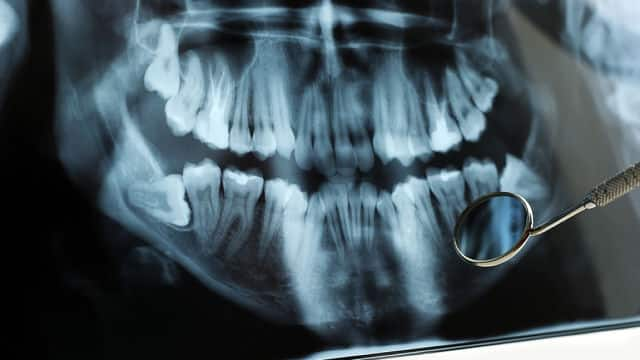

Se il dentista consiglia di estrarre i denti del giudizio, non c'è nulla da temere... E nulla da perdere. Quando i terzi molari iniziano a nuocere alla salute orale, infatti, rimuoverli è sicuramente la decisione più sensata. A patto di osservare alcune indicazioni post-operatorie, indispensabili per guarire correttamente e prevenire eventuali complicanze.

Ogni anno, milioni di persone si sottopongono a interventi di estrazione dei denti del giudizio e nonostante il temporaneo sanguinamento, il gonfiore, le ecchimosi e il fastidio successivi all’operazione, la maggior parte dei pazienti guarisce rapidamente. Una delle complicanze osservate con maggiore frequenza, ma anche una delle più facili da prevenire, è l’alveolite secca.